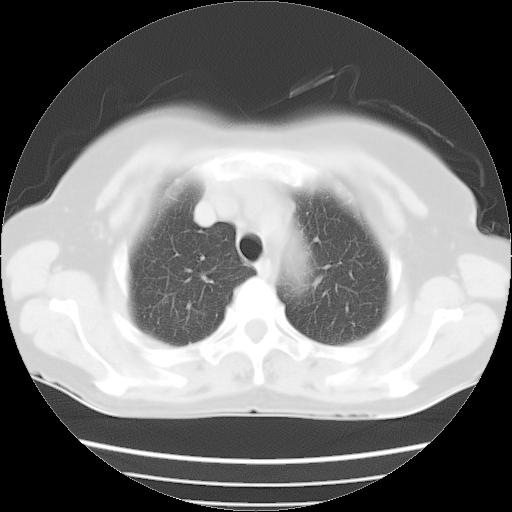

以下是引用夏季在2007-9-18 11:00:00的发言:[br]1。右肺肿块,周围有短毛刺,肺门侧有血管与其相连,胸壁侧有胸膜凹陷征,考虑周围性肺癌 2。左侧甲状腺软组织肿块,内有高密度钙化灶,考虑左侧甲状腺腺瘤。

以下是引用卜一在2007-9-18 14:41:00的发言:[br]右肺肿块:毛刺+胸膜凹陷征+供血血管+浅分叶+强化。支持:周围性肺癌 !另:左侧甲状腺腺瘤!